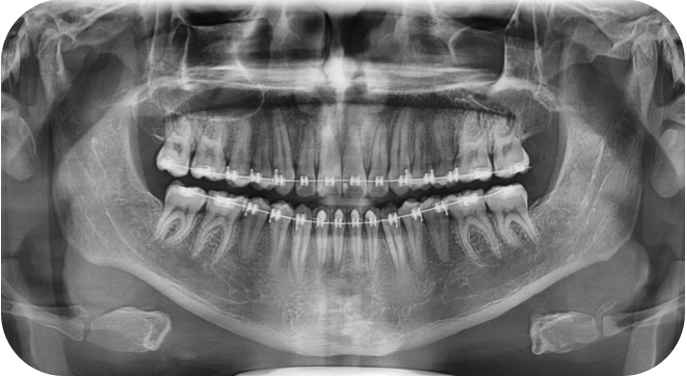

En la radiografía panorámica se observa simetria de las ramas mandibulares, presencia de 32 OD erupcionados, obstruccion parcial de la fosa nasal izquierda y seno maxilar izquierdo reducido.

Fig 4.2 Radiografia panoramica inicial

Radiografías panorámicas de seguimiento con el objetivo de observar el paralelismo radicular e iniciar con el anclaje esquelético.

Fig 10. Panoramica inicial

Fig 10.1 Panoramica 9 meses de tratamiento